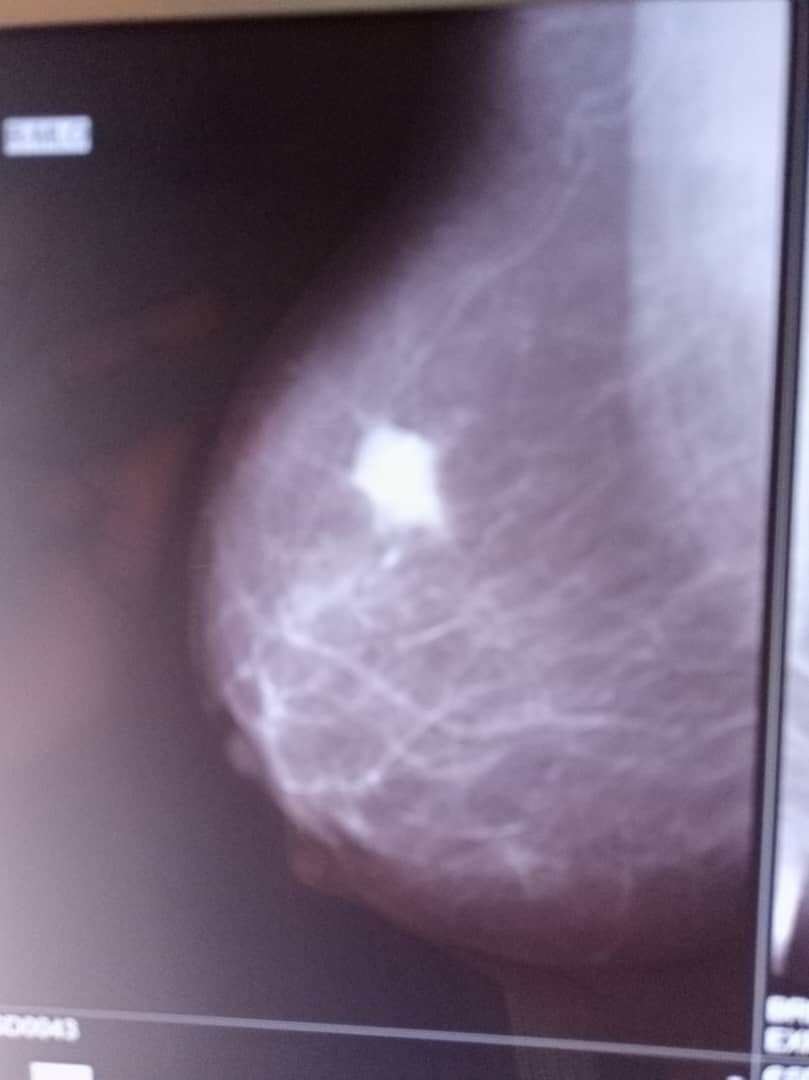

- Mammography

Mammography utilizes low dose x-rays to generate images of the breasts in search for abnormalities especially cancer at its early stage. Although mostly done for women, to screen for and diagnose breast cancer, it is also done occasionally for men with suspicious breast swellings to exclude possible breast cancer.